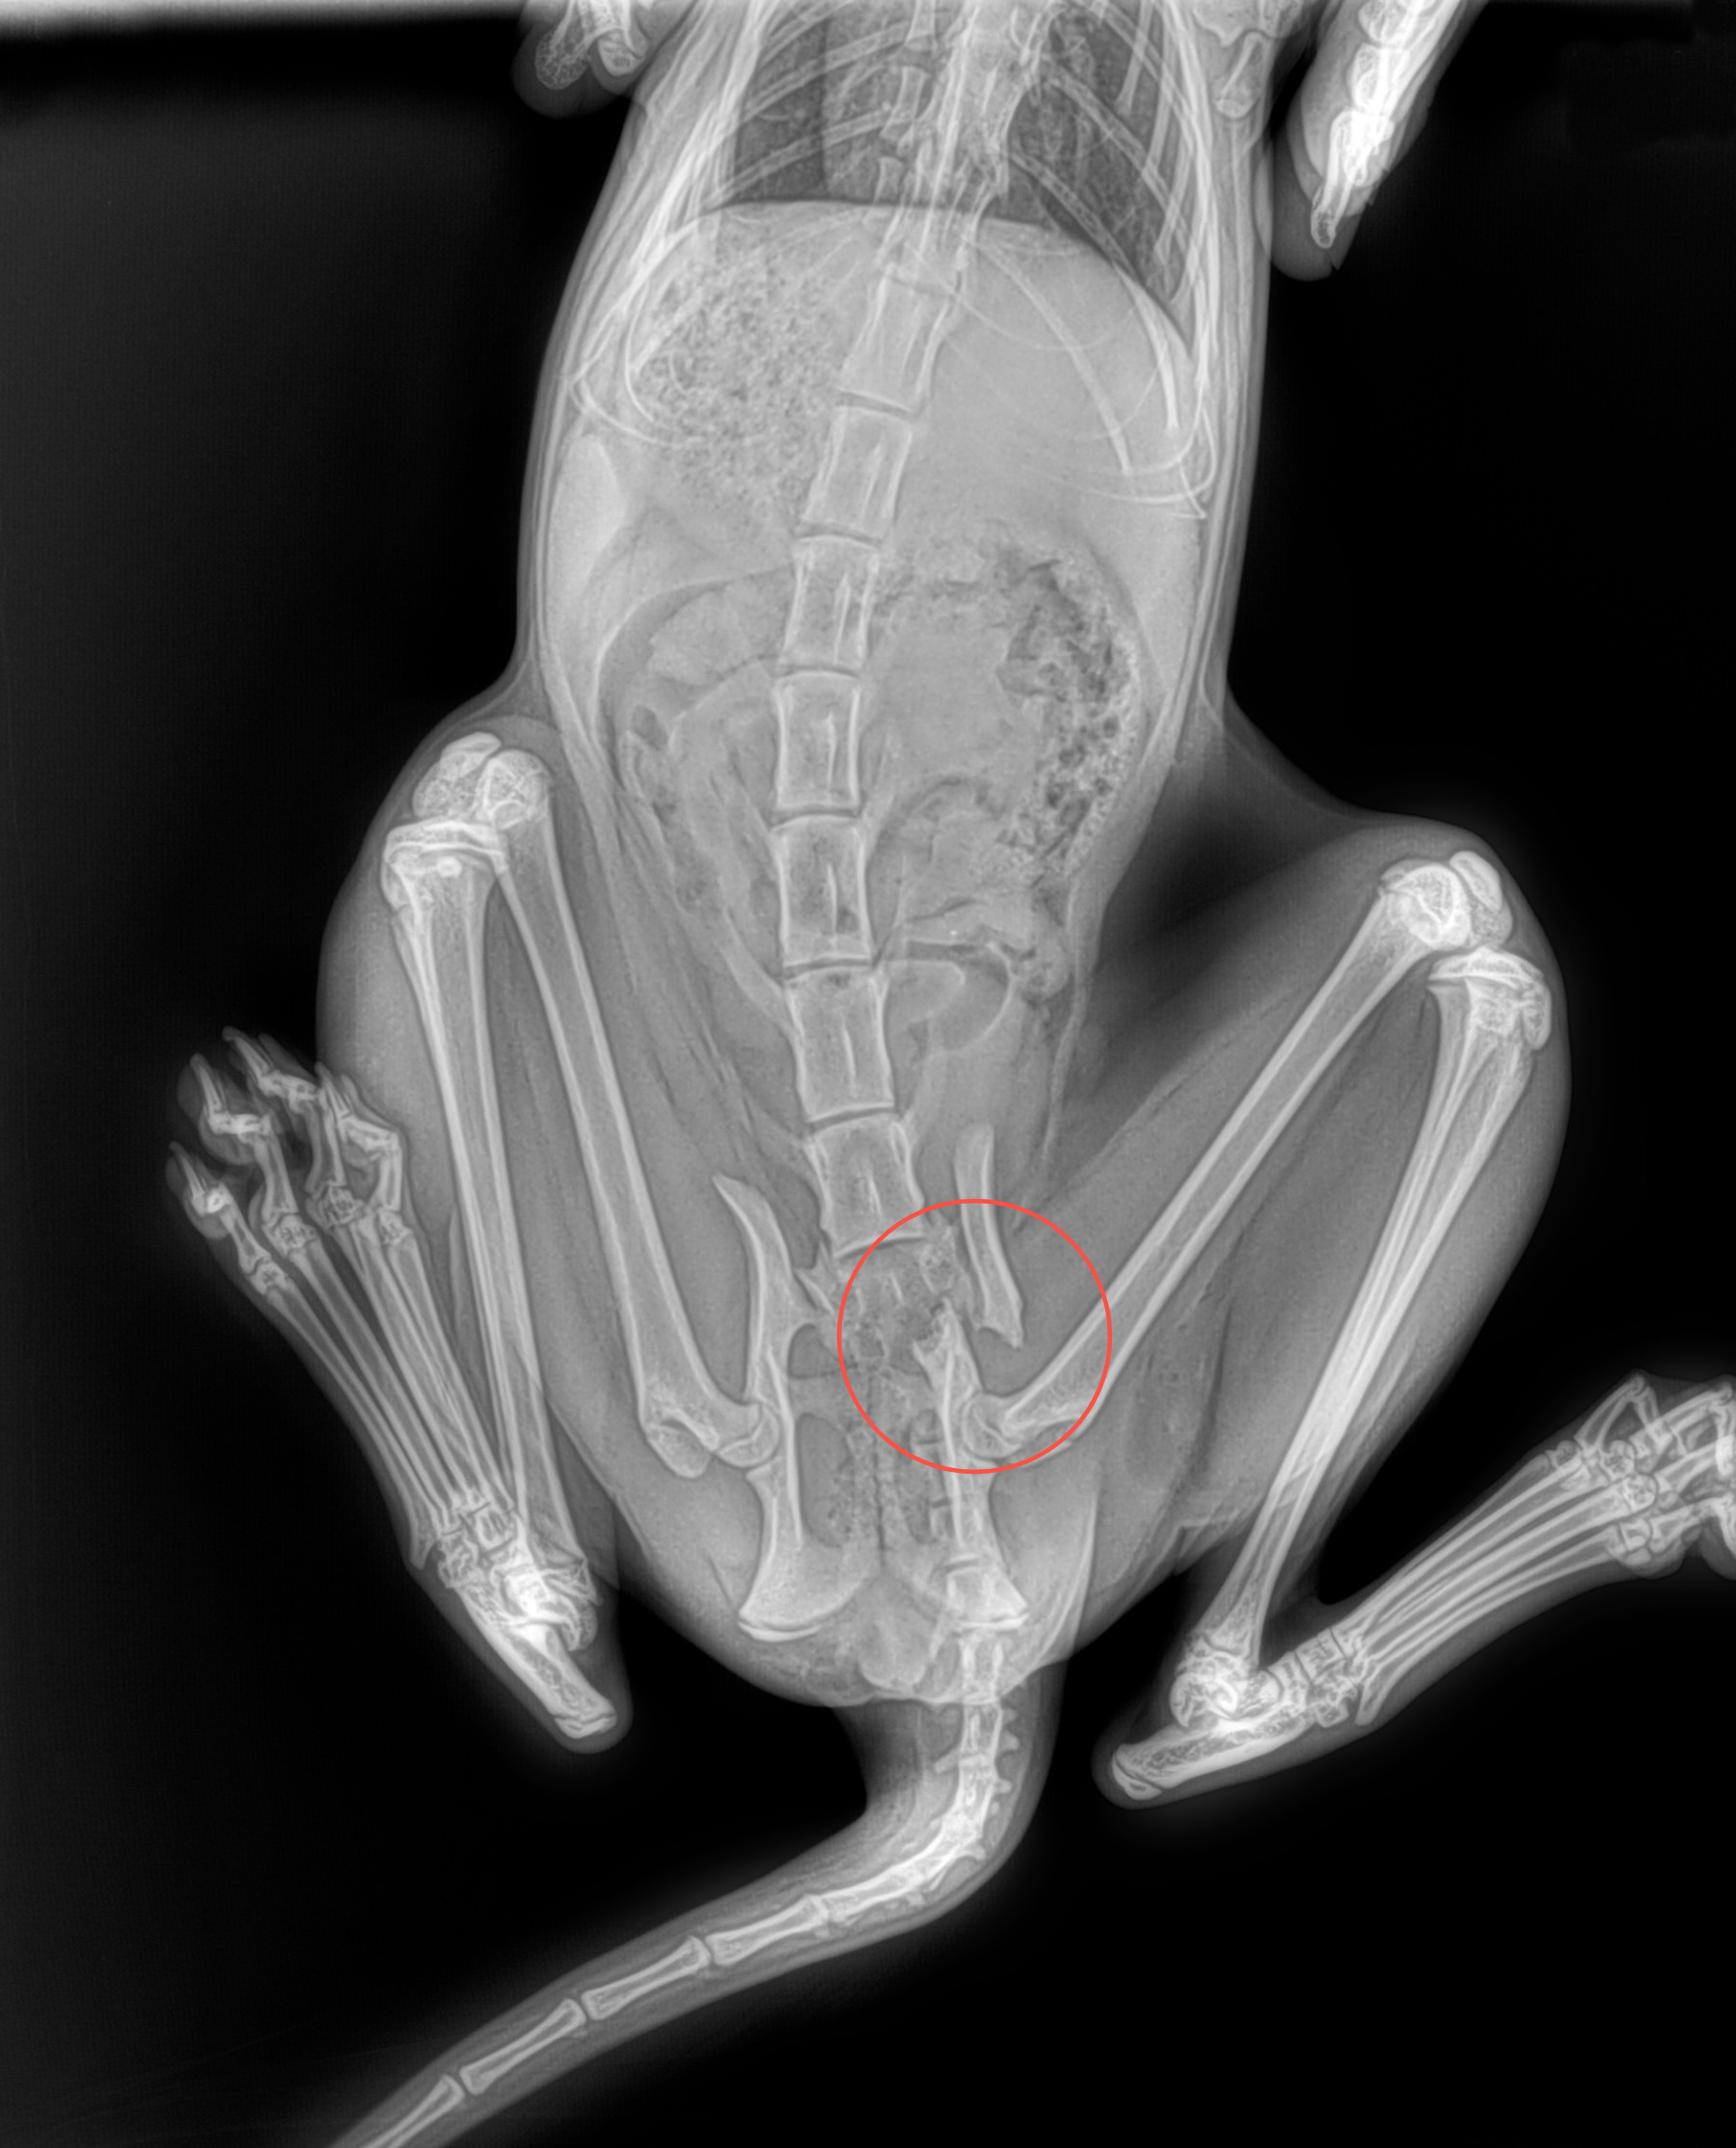

Radiología Digital como Herramienta Complementaria en el Dictamen de Bienes Muebles